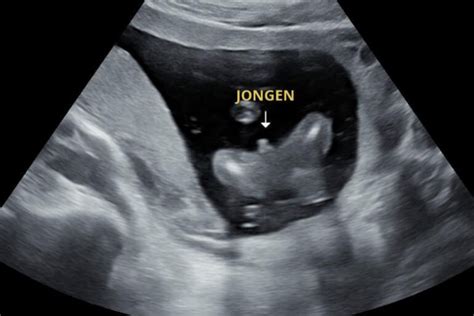

- Zwangerschapsdagboek: Het bijhouden van een dagboek waarin ervaringen, kwaaltjes, mijlpalen en echo-foto's worden vastgelegd, vormt een persoonlijke herinnering. Dit dagboek kan later gedeeld worden met het kind.